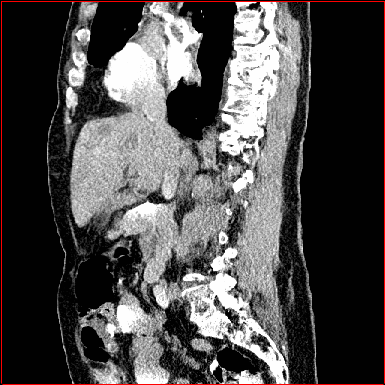

Figure 3 shows the generalizability of MAISI-v2 ControlNet for different body regions and voxel sizes. Figure 4 shows qualitative results for MAISI-v2 ControlNet on 5 types of tumors.

Liver Tumor

0.75×0.75×0.50.75\times 0.75\times 0.5

mm

512×512×768512\times 512\times 768

Figure 4: MAISI-v2 segmentation-guided results for five types of tumors. We show results for different voxel spacing and volume size to demonstrate the flexibility of MAISI-v2. Different Hounsfield Unit window is used to better show the contrast between tumor and normal tissues.